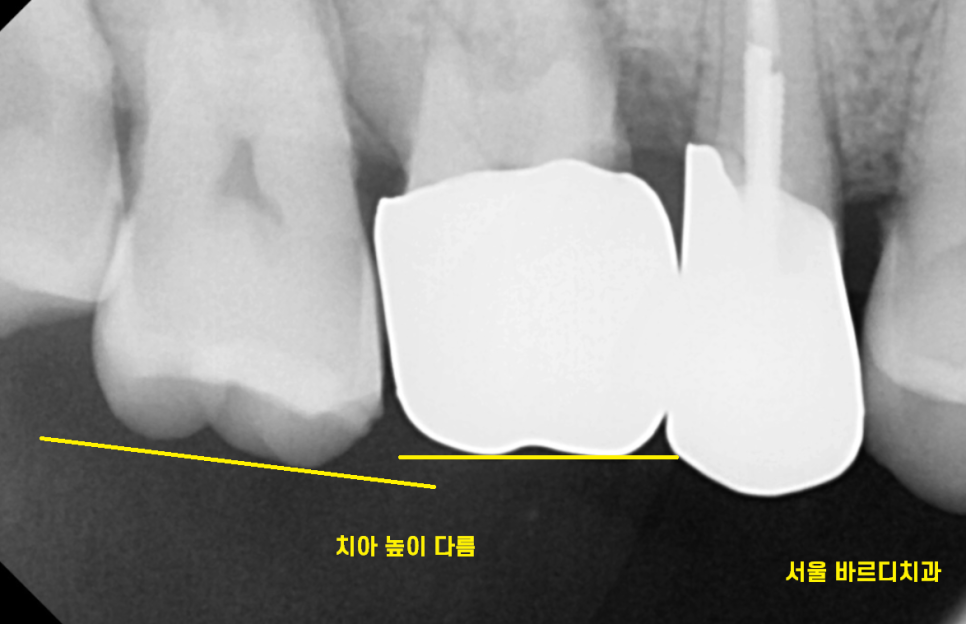

23.07.04

실제로도 미세하게

치아 높이가 다르셨어요~